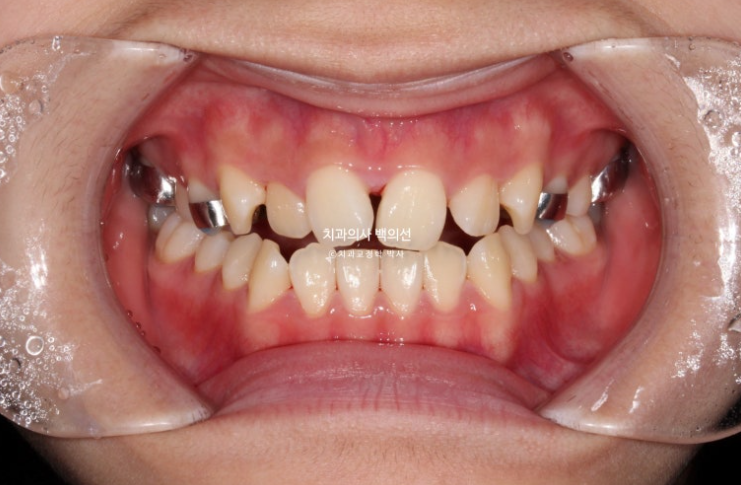

23.10

사진처럼 양쪽 어금니가 모두 거꾸로 물릴 정도로 위턱이 좁다면 악궁확장장치를 먼저 따로 써야 합니다.

치아를 품는 뼈의 면적을 늘려주어야 잇몸에 무리없이 좋은 결과가 나옵니다.